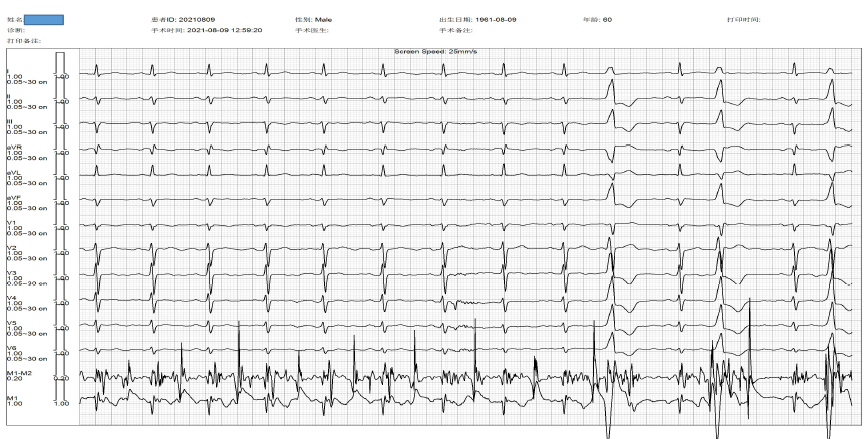

男性,21岁,因“体检发现室早1月”入院,Holter提示室性异位搏动,总数12215个。入院后体表心电图V1导联QRS呈rS形,下壁导联Ⅱ、Ⅲ、aVF导联的QRS呈R形,Ⅰ导联QRS呈m形,初判为右室流出道起源的室早。

图片

术前心电图

手术过程中,首次标测在肺动脉右瓣瓣下标测到明显提前体表28ms最早点,多点消融后无明显变化;再次应用Columbus®系统,在肺动脉左瓣瓣下标测到明显提前体表34ms最早点,消融后室早明显减少,但不能完全消失。观察数分钟后考虑股动脉穿刺并进行激动标测,相较前两次标测最早点领先体表时间,未发现主动脉内领先体表较好的点。故在此返回左侧尝试标测左室流出道间隔部,标测领先体表28ms,相较不如前三次标测领先时间,靶点是近场电位,尝试消融6s后早搏消失,遂继续消融120s结束手术。

术中应用Columbus®系统标测

消融成功后心电图恢复正常